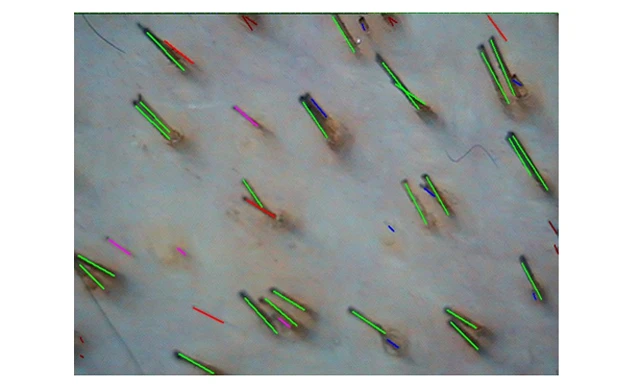

зеленым цветом обозначены нормальные волосы (терминальные), красным цветом – диспластичные (веллусные).

Фототрихограмма при андрогенетической алопеции

Анаг.-51%(дисп.50%) Тел.-48%(дисп.52%) плотность волос 212,28 на см. кв.

(норма 300±20/см?)

Анаг.-81%(дисп.8%) Тел.-19%(дисп11%) плотность волос 262,55 на кв. см.

(норма 195±13/см?)

Наблюдается снижение плотности, высокое процентное содержание телогеновых и диспластичных волос в теменной зоне, а в затылочной зоне эти показатели остаются в норме.